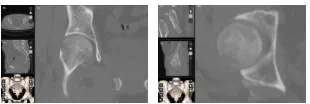

术后一个月CT

术后两月,影像检查。

术后影像学随访显示骨折愈合良好,无坏死征象,这充分证明了缝匠肌内侧入路数字化设计结合可吸收棒固定术的卓越疗效。